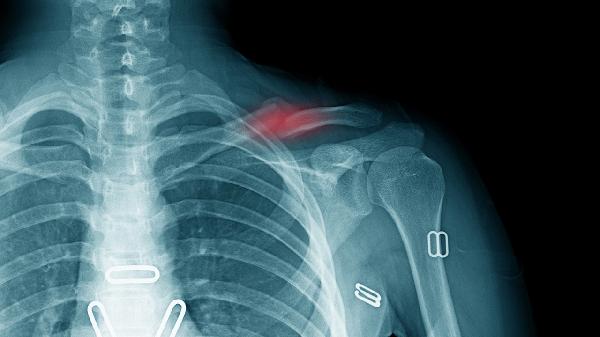

4、胸锁关节紊乱:

胸锁关节脱位或退行性变可能引发局部隐痛,关节活动时有弹响感。需通过X线或CT确诊,轻症可通过关节复位和固定治疗,反复脱位需手术修复。